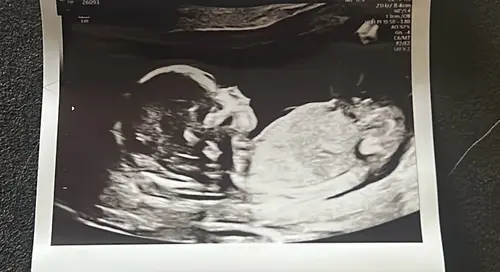

Iemand een idee? Ik heb echt geen idee waar ik moet kijken ☺️

Ik denk een jongen

Ja denk ook jongen! Je ziet iets uitsteken